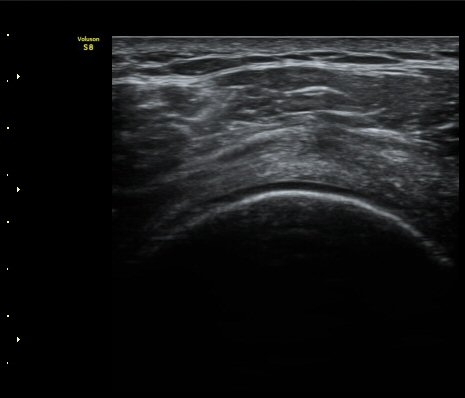

ÀδëÀÇ ºñÈİ¡ °üÂûµÈ´Ù(»çÁø 4). ±Ø»ê°ÇÀÇ Á¾´Ü¸é°Ë»ç¿Í Ⱦ´Ü¸é°Ë»ç¿¡¼­ ±Ø»ê°Ç ½ÉÃþ¿¡

Àú¿¡ÄÚ º´º¯ÀÌ °üÂûµÈ´Ù(»çÁø 5, 6).